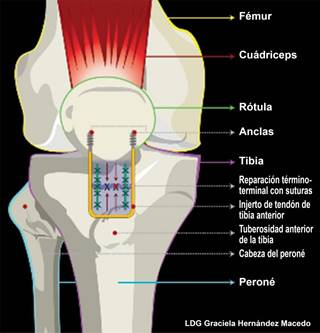

El primer tiempo quirúrgico se realizó 48 horas después del trauma inicial; consistió en la reparación primaria del TP con suturas, utilizando Fiberwire® (Arthrex, Naples, FL, EUA) y reforzamiento con aloinjerto del tibial anterior en forma de “U” (Biograft®), fijado de manera transósea a la patela con dos anclas SwiveLock® 4.75 × 19.1 mm (Arthrex, Naples, FL, EUA) (Figuras 3 y 4); se realizó la reparación del LCM con dos anclas Corkscrew® 5 ×15.5 mm (Arthrex, Naples, FL, EUA) a la porción profunda, reforzado con dos anclas PushLock® 3.5 × 19.5 mm (Arthrex, Naples, FL, EUA) a la porción superficial. Fue egresado con una rodillera mecánica y apoyo diferido; se le indicó apoyo parcial a partir de la segunda semana. Fue canalizado a rehabilitación a la cuarta semana, liberando de manera gradual el arco de movilidad de la rodillera; con ello se permitió la cicatrización e integración del injerto tendinoso en el tendón patelar y la reparación ligamentaria del LCM.

Figura 4: Diagrama que muestra la configuración en “U” del aloinjerto de tibial anterior al tendón patelar.

El procedimiento quirúrgico más utilizado para el TP es la reparación primaria (término-terminal) mediante el uso de suturas (absorbibles y no absorbibles);4,8,10 algunos autores refieren el empleo de banda de tensión con alambre (cerclaje);3,5 Gülabi D y su equipo6 mencionan el injerto autólogo de isquiotibiales para la reconstrucción en forma de “8” y túneles transóseos en lesiones crónicas. Nuestro manejo dentro del primer tiempo quirúrgico fue la reconstrucción de las estructuras extraarticulares; esto es, la reconstrucción del TP con supersuturas y reforzamiento con aloinjerto del tibial anterior en forma de “U”, fijado de manera transósea a la patela con dos anclas y anastomosis término-terminal del tendón (Figura 4); plastia del LCM con dos anclas a la porción profunda y dos anclas a la porción superficial.